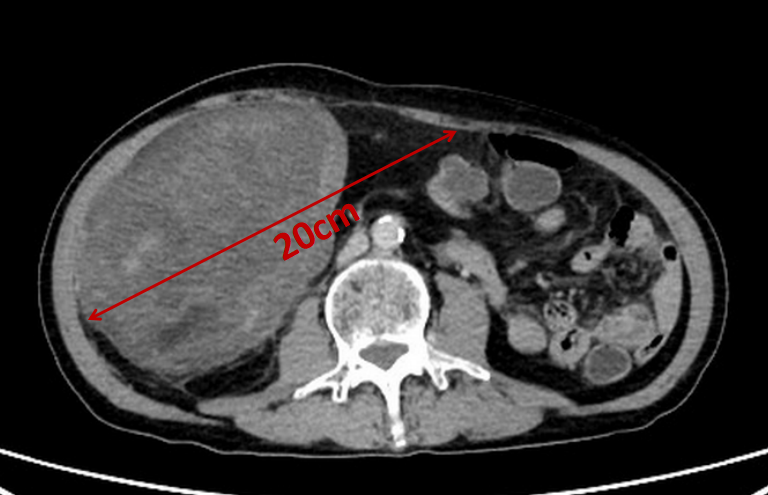

肚子只是微微发胖,居然暗藏一个西瓜大的肿瘤!